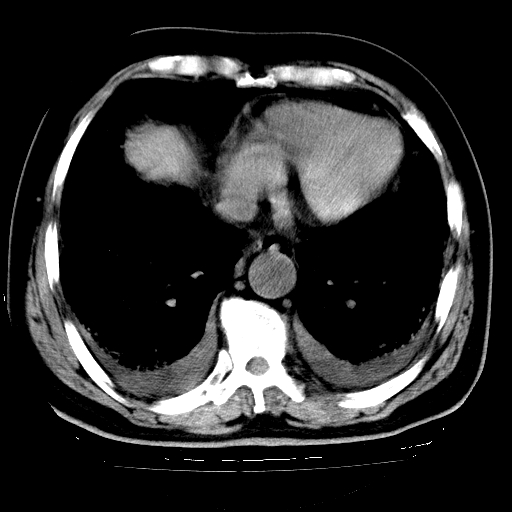

男,68岁,咳嗽、胸闷、发烧三天,查体:双肺散在湿罗音。

首先考虑特发型肺间质纤维化;两侧少量胸腔积液。

依据:1、两肺广泛条索状、网格状、蜂窝状改变。

1.双肺间质纤维化并感染;

2.双肺慢支炎肺气肿;

3.支扩并感染;

4.肺原性心脏病;

5.双侧胸腔少量积液;双侧胸膜增厚。